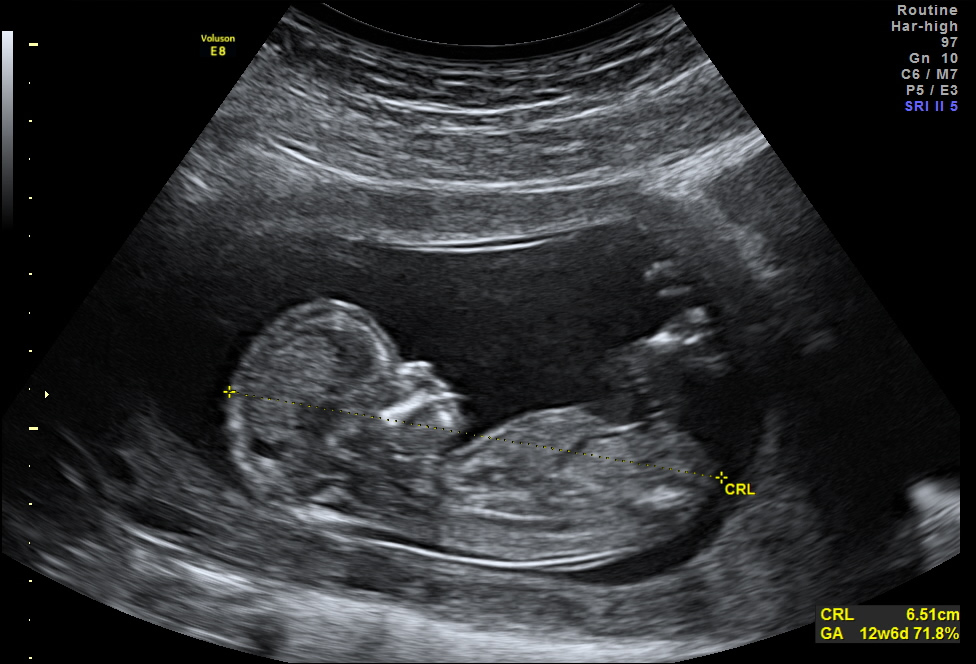

La Neurosonografía Fetal se refiere a la evaluación del Sistema Nervioso Central por Ultrasonidos: cráneo y su contenido (cerebro, ventrículos, tallo, cerebelo, etc.) y de la columna vertebral y su contenido (vértebras, médula espinal, líquido cefalorraquídeo, etc.).

La cabeza y la columna vertebral son los elementos que con mayor facilidad se identifican en vida embriofetal y además, son el asiento de una gran cantidad de anomalías congénitas diagnosticables durante la sonografía obstétrica; las anomalías del SNC se encuentran dentro de las anomalías más frecuentes del ser humano con un promedio de 1:1000 nacidos vivos (0.1%) y una prevalencia en vida adulta que podría rondar el 1% debido a la presencia de malformaciones no diagnosticables en vida fetal y/o que progresan en vida posnatal hasta hacerse clínicamente significativas o ser hallazgos casuales durante la evaluación del SNC por otras causas.